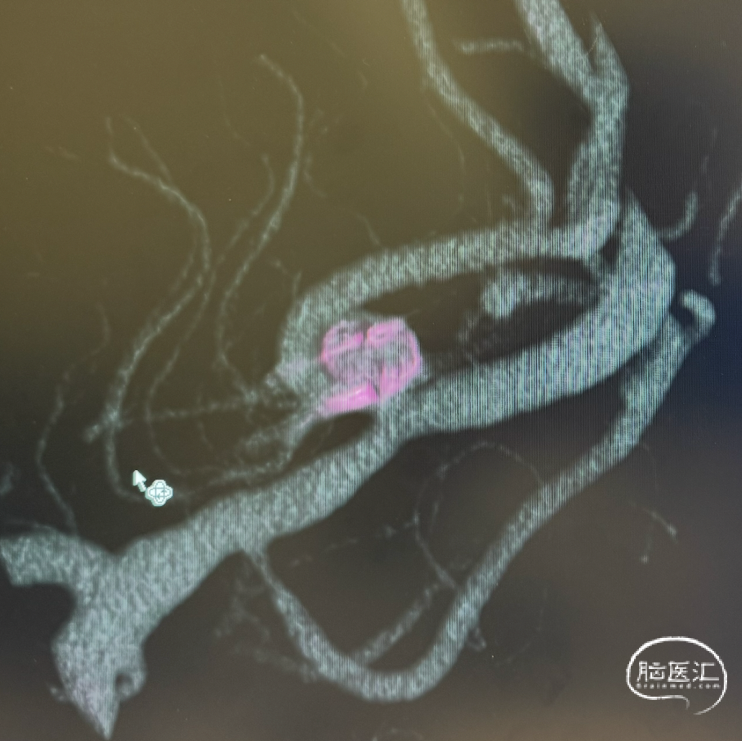

三维旋转图像:左侧大脑中动脉早额支起始部囊性动脉瘤。

动脉瘤参数:最大径4.4mm,瘤高3.5mm,瘤颈宽3.5mm,载瘤动脉直径1.3mm。

术后三维重建及WEB™融合后图像,可见WEB™贴壁良好。

WEB™装置型号匹配:根据动脉瘤参数(3.8×3.5mm),选择WEB™ SL 4mm*2mm型号,其设计特点能适应分叉部解剖,但需注意成角可能影响装置展开。术前需通过三维影像精确测量瘤颈宽度与瘤体深度,避免因尺寸偏差导致贴壁不良或移位。

WEB™释放的实时评估:在成角部位,装置展开易受血流冲击影响。需通过多角度造影动态观察WEB™形态,重点确认瘤颈覆盖是否完全、尾端是否充分展开。本例通过反复调整,最终实现装置稳定贴壁,术后利用西门子自带多容积三维重建,分析扰流装置的位置,证实了技术操作的可靠性。